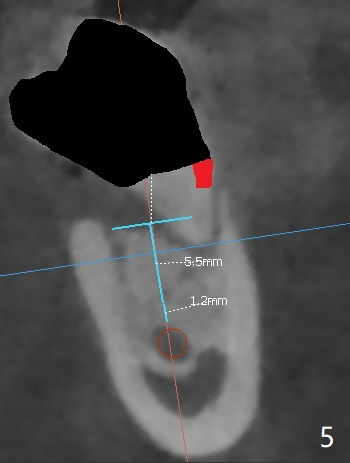

A 44-year-old woman has severe chronic periodontitis. The tooth #18 is nonsalvageable (Fig.1). To avoid distal end guide, do not remove the 3rd molar in the lab. While a 5x7.3 mm implant is long for the site (Fig.2), a 5.5x5.5 mm one seems to be a better option (Fig.3). The latter could be 1 mm more coronal. The last drill (5.0 mm) and cortical tap will be used free hand. #17 will be extracted after implantation. Since the patient is reluctant to have #16 to be extracted, place #18 implant ~ 1-2 mm more distal so that the implant crown will have some occlusal contact with #16. Prepare IS extra wide kit. Or use a 8/7 mm trephine bur to harvest cortical bone from the ramus. Drill a hole for fixation screw before removing the onlay graft. Keep the 3rd molar if possible. Prepare Tatum spacers to measure the size of #18 socket opening. In fact, the lab is able to place a 5x7.3 mm implant with 2 thread exposure buccal. Prepare sticky bone and PRFx2 to prevent periimplantitis. Soak one O-ring in case of having to extend osteotomy by .5 mm (next longer drill (1.5 mm) - 1 mm (O-ring)). For socket shield at #18 (Fig.6 *), section the tooth horizontal with a new surgical fissure bur (Fig.4 black area), use an end-cutting bur to remove buccal edge of the root (Fig.5 red area) and finally remove the lingual portion of the root (Fig.6 pink). Insert 4.5x10 mm dummy implant to determine whether the final implant 5x7.3 mm (bottom of the 1st line) will probably contact the shield. Buccal view of the lingually inclined 2nd molar (Fig.7). After removal of the crown of the 2nd molar (Fig.8 occlusal view), the lingual portion of the root is resected (Fig.9 black area). CT coronal sections show socket shield formation (Fig.10,11).